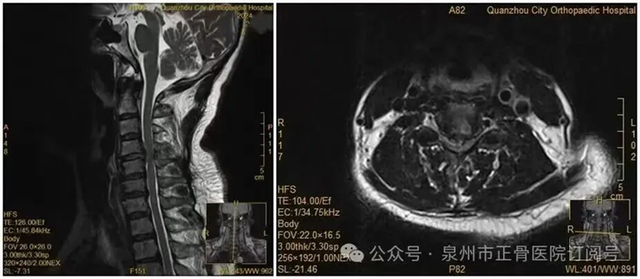

Bác sĩ cho biết, phim chụp cho thấy đĩa đệm cổ đã thoát vị rất lớn , hoàn toàn đủ chỉ định phẫu thuật, nên khuyến cáo bà cần can thiệp sớm. Tuy nhiên, do lo ngại rủi ro, bà Vương kiên quyết chọn điều trị bảo tồn , không phẫu thuật.

Không ai ngờ rằng, ngay tối hôm đó , trong lúc trở mình lấy điện thoại, hai tay bà đột ngột mất hoàn toàn cảm giác . Kiểm tra cho thấy sức cơ các nhóm cơ chính giảm xuống mức 0-1 , được chẩn đoán liệt .

Các bác sĩ nhận định, khi trở mình, khối đĩa đệm đã thoát vị tiếp tục chèn ép mạnh vào tủy sống , gây ra tình trạng cấp tính. Rất may, sau khi được phẫu thuật khẩn cấp và phục hồi chức năng, chức năng vận động của bà đang dần hồi phục .